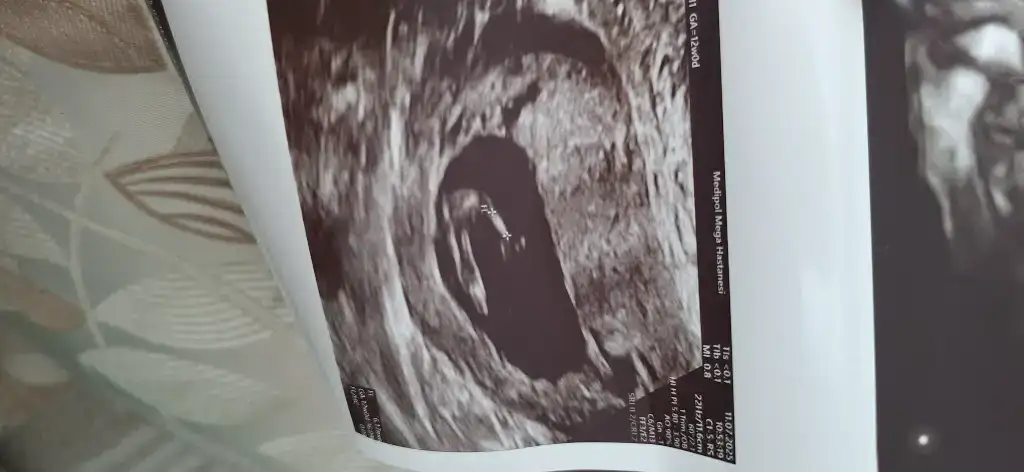

Rica etsem benimkini de bakar msınNub teorisine göre çıkıntı erkek çıkıntısı degil düz ve 3 çizgi yani bana sorarsan yüzde 80 kız haklı çıkarsam yaz lütfen tersi olursada yaz ama![]()

Elbette paylaşacağım. :) fetal dna 10 güne çıkarNub teorisine göre çıkıntı erkek çıkıntısı degil düz ve 3 çizgi yani bana sorarsan yüzde 80 kız haklı çıkarsam yaz lütfen tersi olursada yaz ama![]()